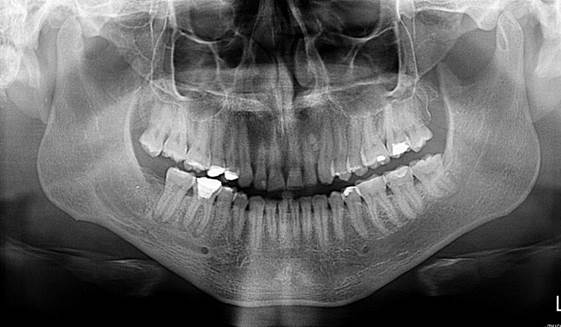

Sse procede a evaluar y analizar ortopantomografia inicial, lo cual hace referencia a una lesion de 1,7 cm x 2cm aproximadamente ya que esto es referencial, evaluación de imágenes de TAC,  analisis de informe imagienológico,       exámenes     de laboratorio que arrojan leve aumento de la serie blanca asociada a infección, ya con todos estos datos clinicos e imagienológicos, se  procede a la discusión y planificacion quirúrgica en la que se decide su remocion  completa y no parcial, realizar estudio histopatológico esperando los resultados bajo conducta espectante si amerita un segundo tiempo quirúrgico.

Figura 4.  Ortopantomografia con medidas estimadas del tamaño de la lesión. Fuente Palima (2016).

Figura 7 Ortopantomografía control luego de 8 días del acto quirúrgico Fuente Palima (2016).

Cita 4:

Evaluación, valoración y control, manejo de la sensibilidad, mapeo, donde fue favorable la cicatrización del paciente ya que dejo el hábito del cigarro durante el postoperatorio, no hubo pérdida de la sensibilidad sino un leve aumento de la misma, imagienológicamente se logra observar una cavidad limpia sin restos y con formación ósea normal para los 8 días postquirúrgico.